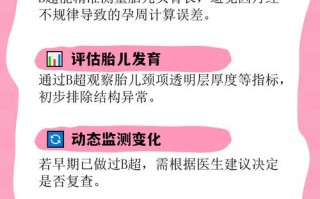

- NT检查(颈项透明层厚度):通过B超测量胎儿颈后部皮肤层的厚度,NT值越厚,胎儿患有染色体异常(包括唐氏综合征)的风险越高。

- 风险提示:如果NT厚度≥ 3.0mm,通常被认为是高风险,医生会建议进行进一步检查。

在孕期的常规B超检查中,医生可能会发现一些与唐氏综合征相关的“软指标”,发现任何一个软指标,都会增加胎儿患染色体异常的风险,但单独一个软指标并不意味着胎儿一定有问题。

- 鼻骨缺失或发育不良:在孕11-13+6周的B超中,如果发现胎儿鼻骨未显示或过短,是唐氏综合征的一个重要软指标。